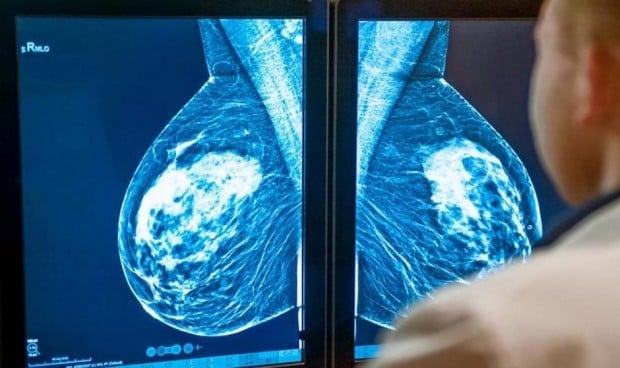

El cáncer de mama HER-2+ es un tipo de cáncer con alta presencia del receptor 2 de factor de crecimiento epidémico humano (HER-2), una proteína que promueve el crecimiento de las células cancerosas. Cuando estos tumores se detectan temprano -antes de que se diseminen a otras áreas del cuerpo-, se extraen mediante cirugía y se tratan con terapias dirigidas a bloquear HER-2. Sin embargo, incluso en los pacientes con buen pronóstico, la combinación con la quimioterapia sigue formando parte del tratamiento estándar para prevenir la reaparición del tumor después de la cirugía.

En el ensayo PHERGain-II se administrará a los pacientes un tratamiento preoperatorio con trastuzumab y pertuzumab, fármacos cirigidos a bloquear HER-2, sin quimioterapia. Los tumores serán escaneados mediante resonancia magnética antes y después del tratamiento para determinar si es posible predecir el nivel de respuesta patológica alcanzada tras el tratamiento mediante la obtención no invasiva de imágenes del tumor. Tras la cirugía, en función de la respuesta a la terapia con trastuzumab y pertuzumab, se continuará el tratamiento con la misma combinación de fármacos o bien con T-DM1 (otro fármaco bloqueante de HER-2), reservando el uso de quimioterapia únicamente a aquellos pacientes que peor hayan respondido al tratamiento preoperatorio y que por tanto cuenten con peor pronóstico.